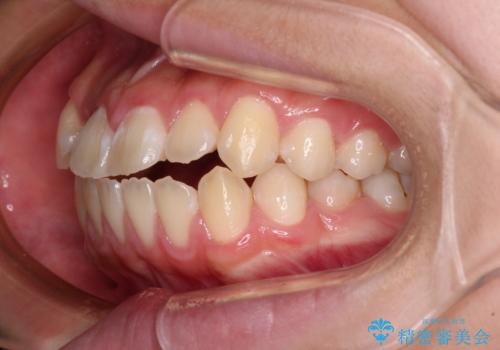

舌の突出癖により上下前歯は接触できず、更には前方に押し出されて出っ歯になっている状態でした。

当初は舌のトレーニングがうまくできていなかったのですが、途中から奏効し、非常に短い期間で治療を終えることができました。